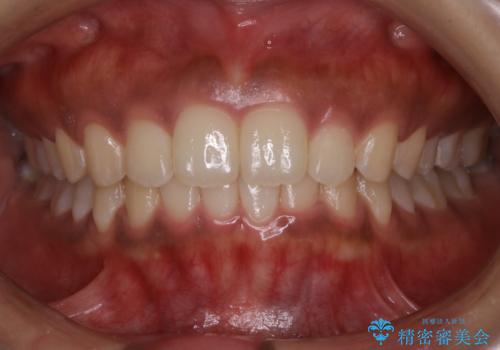

[ 前歯のねじれ・がたつき ] マウスピース矯正

![[ 前歯のねじれ・がたつき ] マウスピース矯正の症例 治療前](https://seimitsushinbi.jp/wp/wp-content/uploads/2024/02/4007c6479f6bce11863dcdd32ed5e39b-500x350.jpg?v=1708502552)

![[ 前歯のねじれ・がたつき ] マウスピース矯正の症例 治療後](https://seimitsushinbi.jp/wp/wp-content/uploads/2024/02/e7a01485e4f4dd0da04705fde4cc34cc-500x350.jpg?v=1708502585)

インビザライン モニター治療 前歯のねじれをまっすぐに